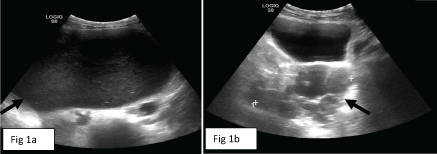

Abdominal US (Figure 1) identified a 23 cm cystic mass in the central abdomen, most probably of right ovarian origin. The lesion contained cystic material with internal echoes; no solid component was identified (Figure 1a). In addition, a multicystic 9 cm mass was demonstrated posterior to the bladder, most probably of left ovarian origin. This second mass had thick septations and various fluid echogenicities (Figure 1b).

Figure 1: Large abdominal cyst with internal echoes at level of mid abdomen (arrow in a) and multicystic left ovarian lesion in the pelvis (arrow in b) on abdominal US examination. View Figure 1

A contrast-enhanced abdominal CT was performed for further investigation of the bilateral ovarian masses. The CT exam demonstrated thin septations and a focal mural thickness in the larger, right ovarian mass. The left multicystic lesion showed minimal mural enhancement with no nodular component. The masses were free of calcifications, and no ascites or lymphadenopathy were seen. Multiple round and oval solid lesions were identified in the left abdomen and pelvis, the largest with a diameter of 3 cm, showing intense homogenous enhancement (Figure 2). No spleen was found in the left upper quadrant, and there were surgical clips in the splenic bed consistent with prior splenectomy.

Figure 2: Contrast-enhanced CT image (sagittal reconstruction) demonstrates multiple, small homogeneously and strongly enhancing solid peritoneal masses (white arrows) of different size in addition to the large right abdominal cyst (black arrow) and smaller multicystic left pelvic mass (arrowhead). View Figure 2